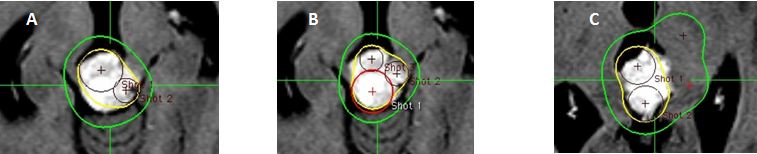

Hình 21: Hình ảnh đặt kế hoạch điều trị cho 2 tổn thương trong một ma trận

Ma trận tính toán được thể hiện (ma trận màu đỏ được chọn). Các shot có thể chỉ được đặt trong ma trận.

Bệnh nhân Ngô Hữu V.; nam, 60 tuổi. Chẩn đoán: Ung thư phổi di căn tiểu não. Chỉ định xạ phẫu: dao gamma quay (RGK) liều 22Gy”

Hình 22: Hình ảnh lập kế hoạch cho 2 khối u: Hình (A)Khối u 2 được bao phủ tốt nhưng khối u 1 không nằm trong đường đồng liều điều trị. Hình (B,C) thêm một shot để bao phủ khối u 1 để tạo ra hiệu quả cần thiết:

Bệnh nhân Ngô Hữu V.; nam, 60 tuổi. Chẩn đoán: Ung thư phổi di căn tiểu não, chỉ định: xạ phẫu dao gamma quay (RGK) liều 22Gy”